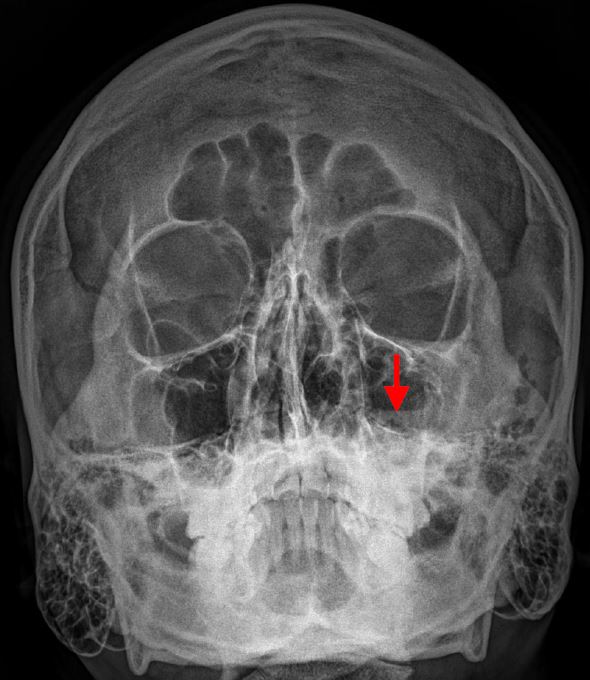

A. Paranasal sinusitis

B.Maxillary abscess

C.Maxillary fracture

D.Maxillary neoplasm